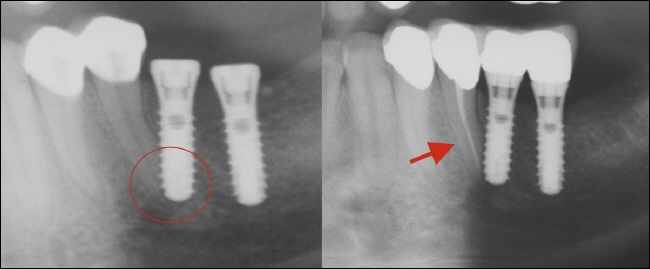

Verletzung von Nachbarzähnen

Fehlende Planung, Routine und anatomische Besonderheiten oder Unkenntnis können dazu führen, dass natürliche Zahnwurzeln in der Nähe der Implantationsstelle beim Implantatlochbohren verletzt werden. Im ungünstigsten Fall bedeutet dies, dass der Zahn einen derartigen Schaden erlitten hat, dass eine Devitalisierung (Abtötung) und anschließende Wurzelfüllung erforderlich ist.

Risikozonen sind prinzipiell überall dort, wo die Wurzeln sehr eng beisammen stehen. Dies ist beispielsweise bei den unteren Frontzähnen oftmals der Fall. Eine entsprechende Planung und eventuell eine Röntgenkontrolle nach der ersten Bohrung können das Risiko deutlich vermindern.